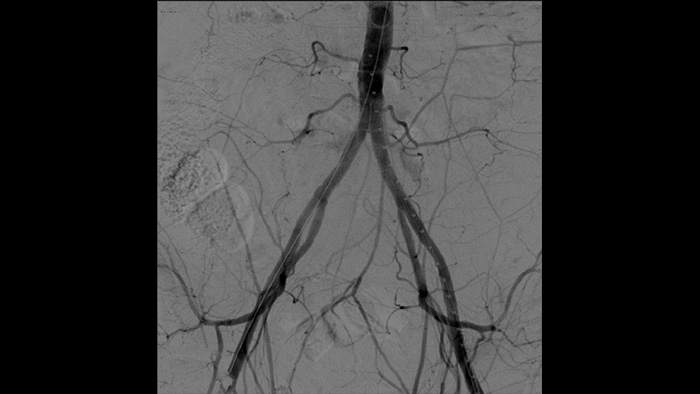

La angiografía por sustracción digital (ASD) se utiliza en procedimientos vasculares intervencionistas para ver con claridad los vasos sanguíneos mediante la eliminación de estructuras que pueden oscurecer la visibilidad de los vasos. La hoja de ruta de fluoroscopia superpone la imagen de contraste sustraída con anterioridad adquirida en la fluoroscopia en vivo, lo que le permite rastrear el dispositivo sin reinyectar el contraste.